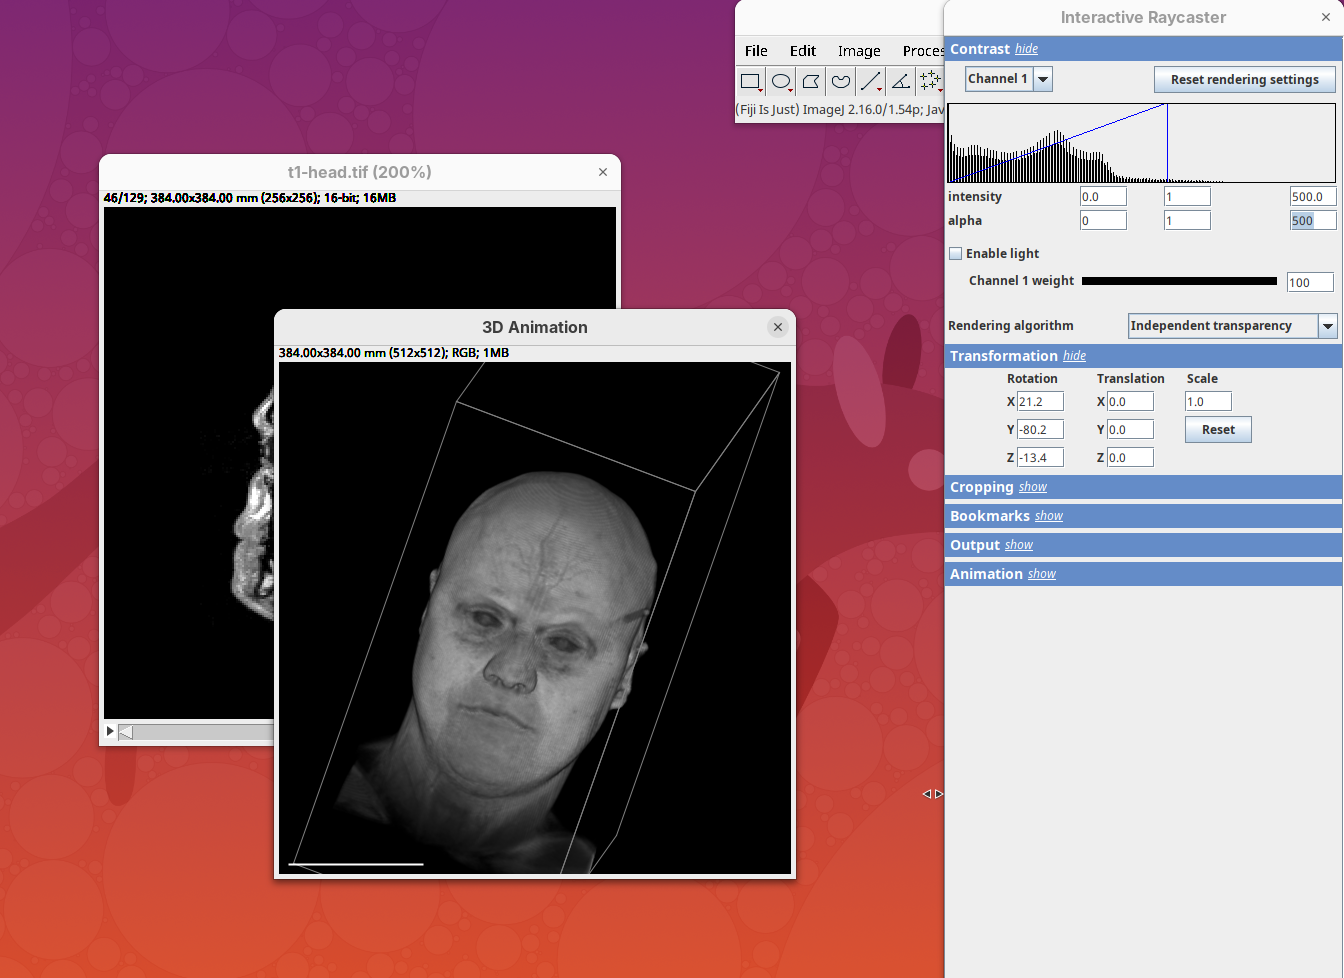

Two new windows will open: 3D Animation with the initial rendering of the data and Interactive Raycaster with all the fields to control the rendering parameters.

Contrast

The Contrast section shows a histogram of pixel intensities of the image for each channel, which we can choose using the dropdown menu. We can set the minimum, gamma, and maximum values for the intensity and alpha (transparency) properties of each pixel. The weight option controls the general opacity of the channel (0=invisible, 100=visible). There’s also more advanced options like lighting and rendering algorithm which we’ll simply use the default states as they are usually good for most use cases.

Adjusting the intensity and alpha values is the most impactful way to improve the 3D rendering. With the intensity setting we can define which pixel value in the image corresponds to total black (minimum) and which corresponds to total white. It’s the same as in the standard Brightness & Contrast tool. By default, 3Dscript will load these values from the original stack. In this case, it loaded min=3 and max=521.

Let’s change these values to see how it impacts the 3D rendering.

- Change the intensity minimum to

250.

You will see that the darkest parts of the rendering will become even darker and no longer visible. We are losing real information from the data; we do not want that.

- Set the

minto0, for now. - Then, change the

maxto250.

The brightest parts of the rendering will become all white. It is so bright that we can no longer resolve details of the surface. We are losing information and also do not want that.

- Set the

maxto500.

Note that when you change an intensity value, the min/max black line in the histogram moves. You can also grab the line and move it manually to change the values.

The blue line represents the alpha values. In 3D rendering, a pixel has a transparency value linked to its intensity. The alpha min defines the value for full transparency and the max the value for full opacity.

- Set the alpha

minto250.

This will make darker pixels more transparent and information gets lost.

- Set it to

0.

By default 3Dscript sets the gamma value of alpha to 2.0. That’s a good default for fluorescence microscopy (see the next dataset below), but since this is MRI data, we need to tweak it a little differently.

- Set the alpha gamma value to

1.0.

Note that this improves the visualization as the head’s surface becomes better visible.

- Now set the alpha

maxto250.

The surface will become even more solid because we are defining that pixels that have a value above 250 will be fully opaque.

- To compare, set alpha

maxto5000.

You will notice that the sample will become more transparent. Even the brain inside the skull will be visible.

- Set alpha

maxback to500.

Generally, setting the intensity and alpha to the same values is a good starting point for optimizing the rendering.